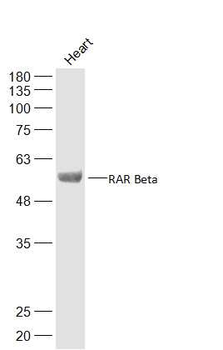

RARB Rabbit Polyclonal Antibody [orb11327]

FC, ICC, IF, IHC-Fr, IHC-P, WB

Bovine, Canine, Gallus, Porcine, Rat

Human, Mouse

Rabbit

Polyclonal

Unconjugated

50 μl, 100 μl, 200 μlTIG2 Rabbit Polyclonal Antibody [orb11481]